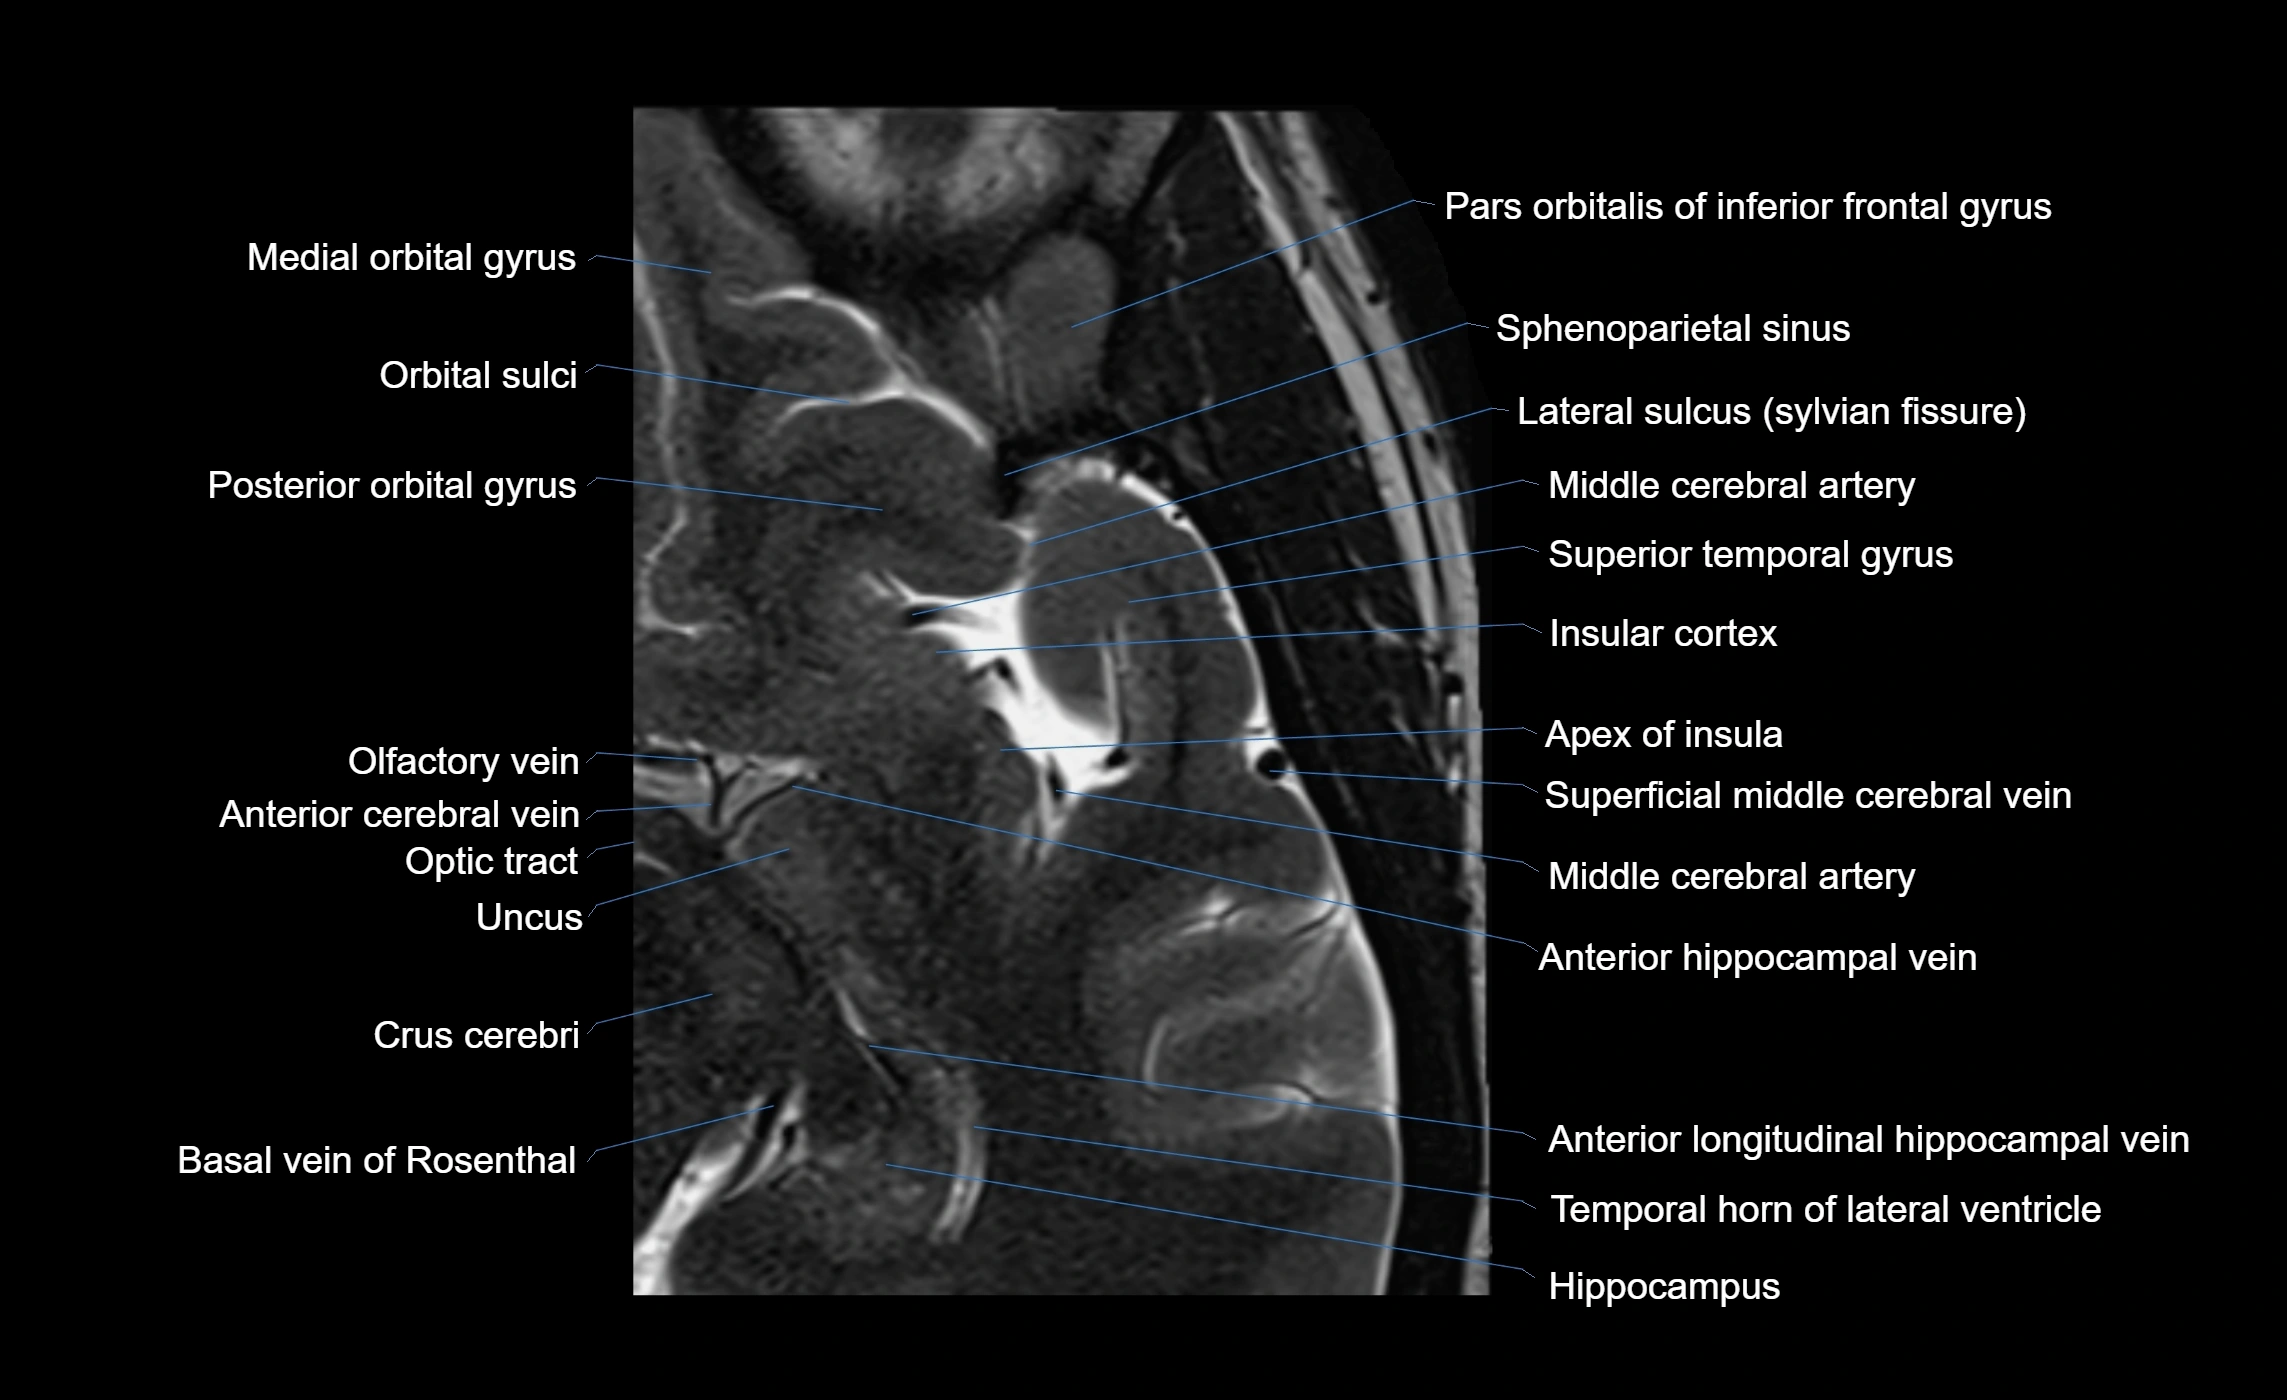

• T1-weighted imaging:

• The Sylvian fissure and its anterior ascending ramus appear as low-signal intensity (dark) CSF-filled clefts between the gyri.

• Clear demarcation between adjacent gray and white matter.

• T2-weighted imaging:

• The fissure, including the anterior ascending ramus, is hyperintense (bright) due to CSF signal.

• Better visualization of the separation between opercular and triangular parts of the inferior frontal gyrus.

• FLAIR imaging:

• The ramus is visualized as a linear dark space (suppressed CSF signal) between the surrounding cortex.

• Adjacent cortical and subcortical abnormalities (e.g., edema or gliosis) can be assessed relative to the ramus.